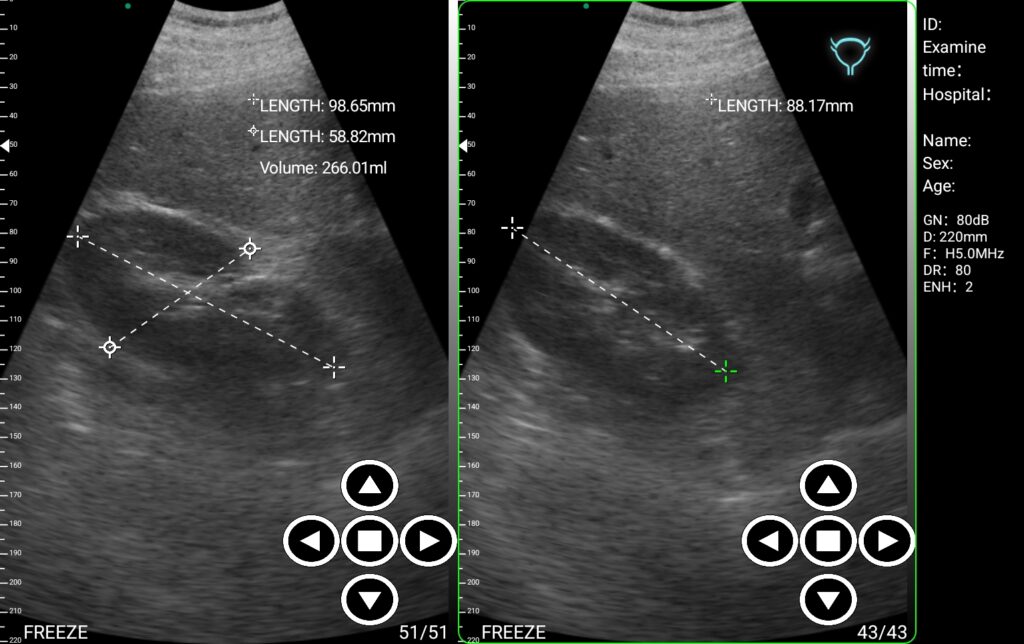

Ουρολογία

Η άμεση πρόσβαση σε απεικονιστικές πληροφορίες σε πραγματικό χρόνο είναι ιδιαίτερα κρίσιμη στην ουρολογία. Η πρώιμη ανίχνευση αποφρακτικών φαινομένων, λίθων, νεοπλασμάτων ή λοιπών παθολογιών καθορίζουν την έκβαση της θεραπευτικής παρέμβασης. Διαβάστε Περισσότερα…